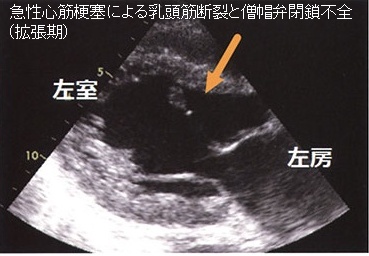

心筋梗塞(右冠状動脈、回旋枝梗塞)による乳頭筋断裂→急性の僧帽弁閉鎖不全(MR)と急性左心不全

甲状腺機能亢進症/バセドウ病、甲状腺機能低下症/橋本病では僧帽弁腱索/乳頭筋断裂の頻度が高い(Endocr Rev. 2005;26(5):704–728.)。

特に循環血液量・心拍出量が増加する甲状腺機能亢進症/バセドウ病では、僧帽弁腱索/乳頭筋断裂を引きおこす危険性が高い。(J Endocr Soc. 2018 Sep 17;2(11):1246-1250.)[Endocrinol Diabetes Metab Case Rep. 2022 Jul 1;2022:22-0298.]